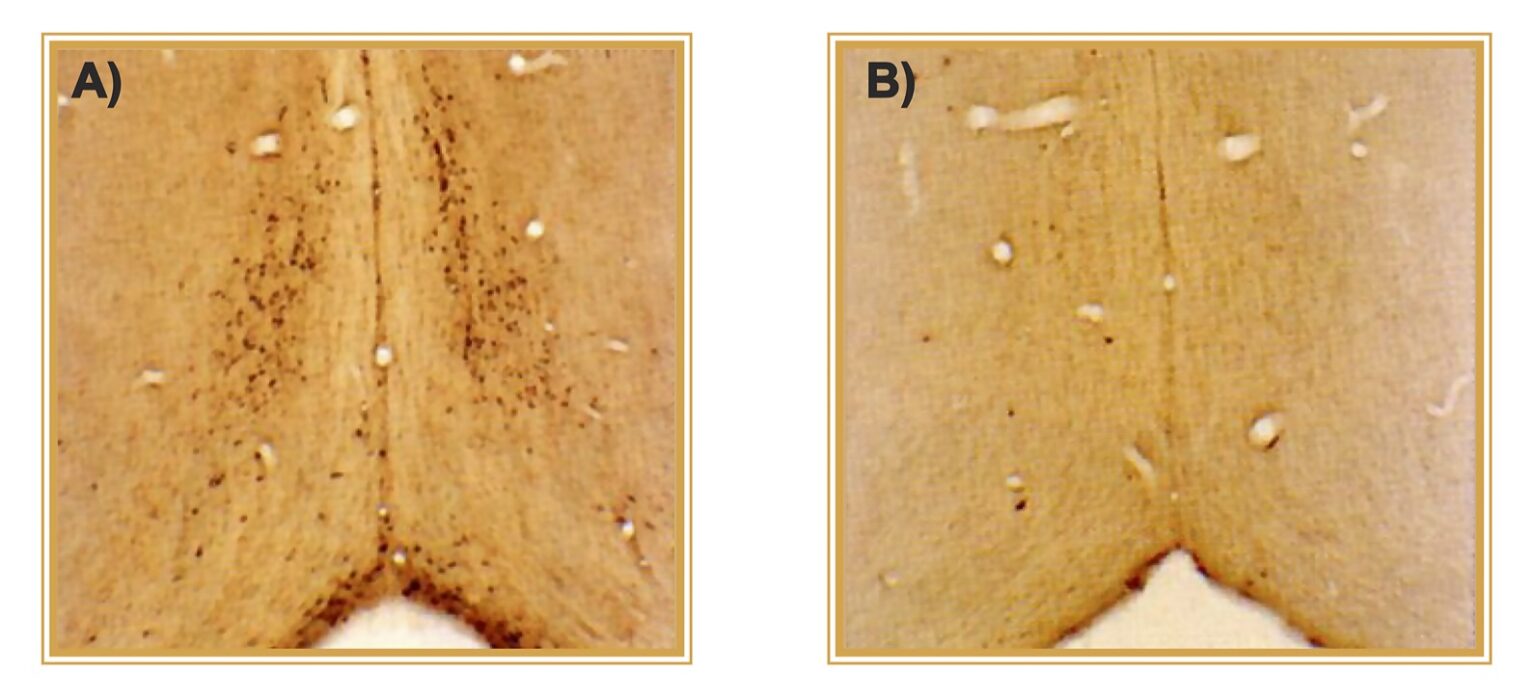

When investigating the origins of targeted toxins (a drug, therapy, or scientific tool directed to unique extracellular target), an appropriate place to begin is with the Nobel Prize-winning work of Paul Ehrlich and his concept of the “magic bullet.” Over 100 years later, the use of targeted toxins to perform molecular neurosurgery has become a vital practice that allows researchers to observe changes in organisms after eliminating a neuronal population. A prime example of this practice is the specific targeting of cholinergic neurons in the basal forebrain to mimic Alzheimer’s Disease (AD). The research tool designed for this purpose is 192-IgG-Saporin, an antibody conjugated to the ribosome-inactivating protein (RIP) Saporin. Researchers have used this targeted toxin for over 30 years. A 2019 publication by Verkhratsky reviews AD models and states this is the only lesion model that specifically targets cholinergic neurons.